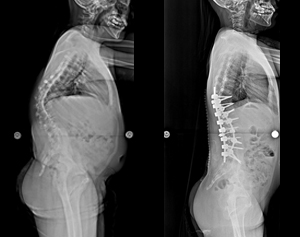

病例三 |

| 術前 |

術後 |

| 側向X光片 |